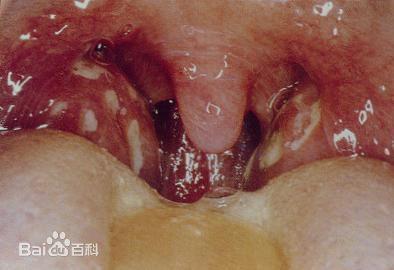

(3)咽喉疾病。细菌病毒感染、受凉、上火、过敏、有害气体刺激、辛辣食物刺激、烟酒过度、用嗓过度等,也会导致喉咙痛,甚至还会伴随咽喉灼热、声音嘶哑等咽喉炎症状的出现。